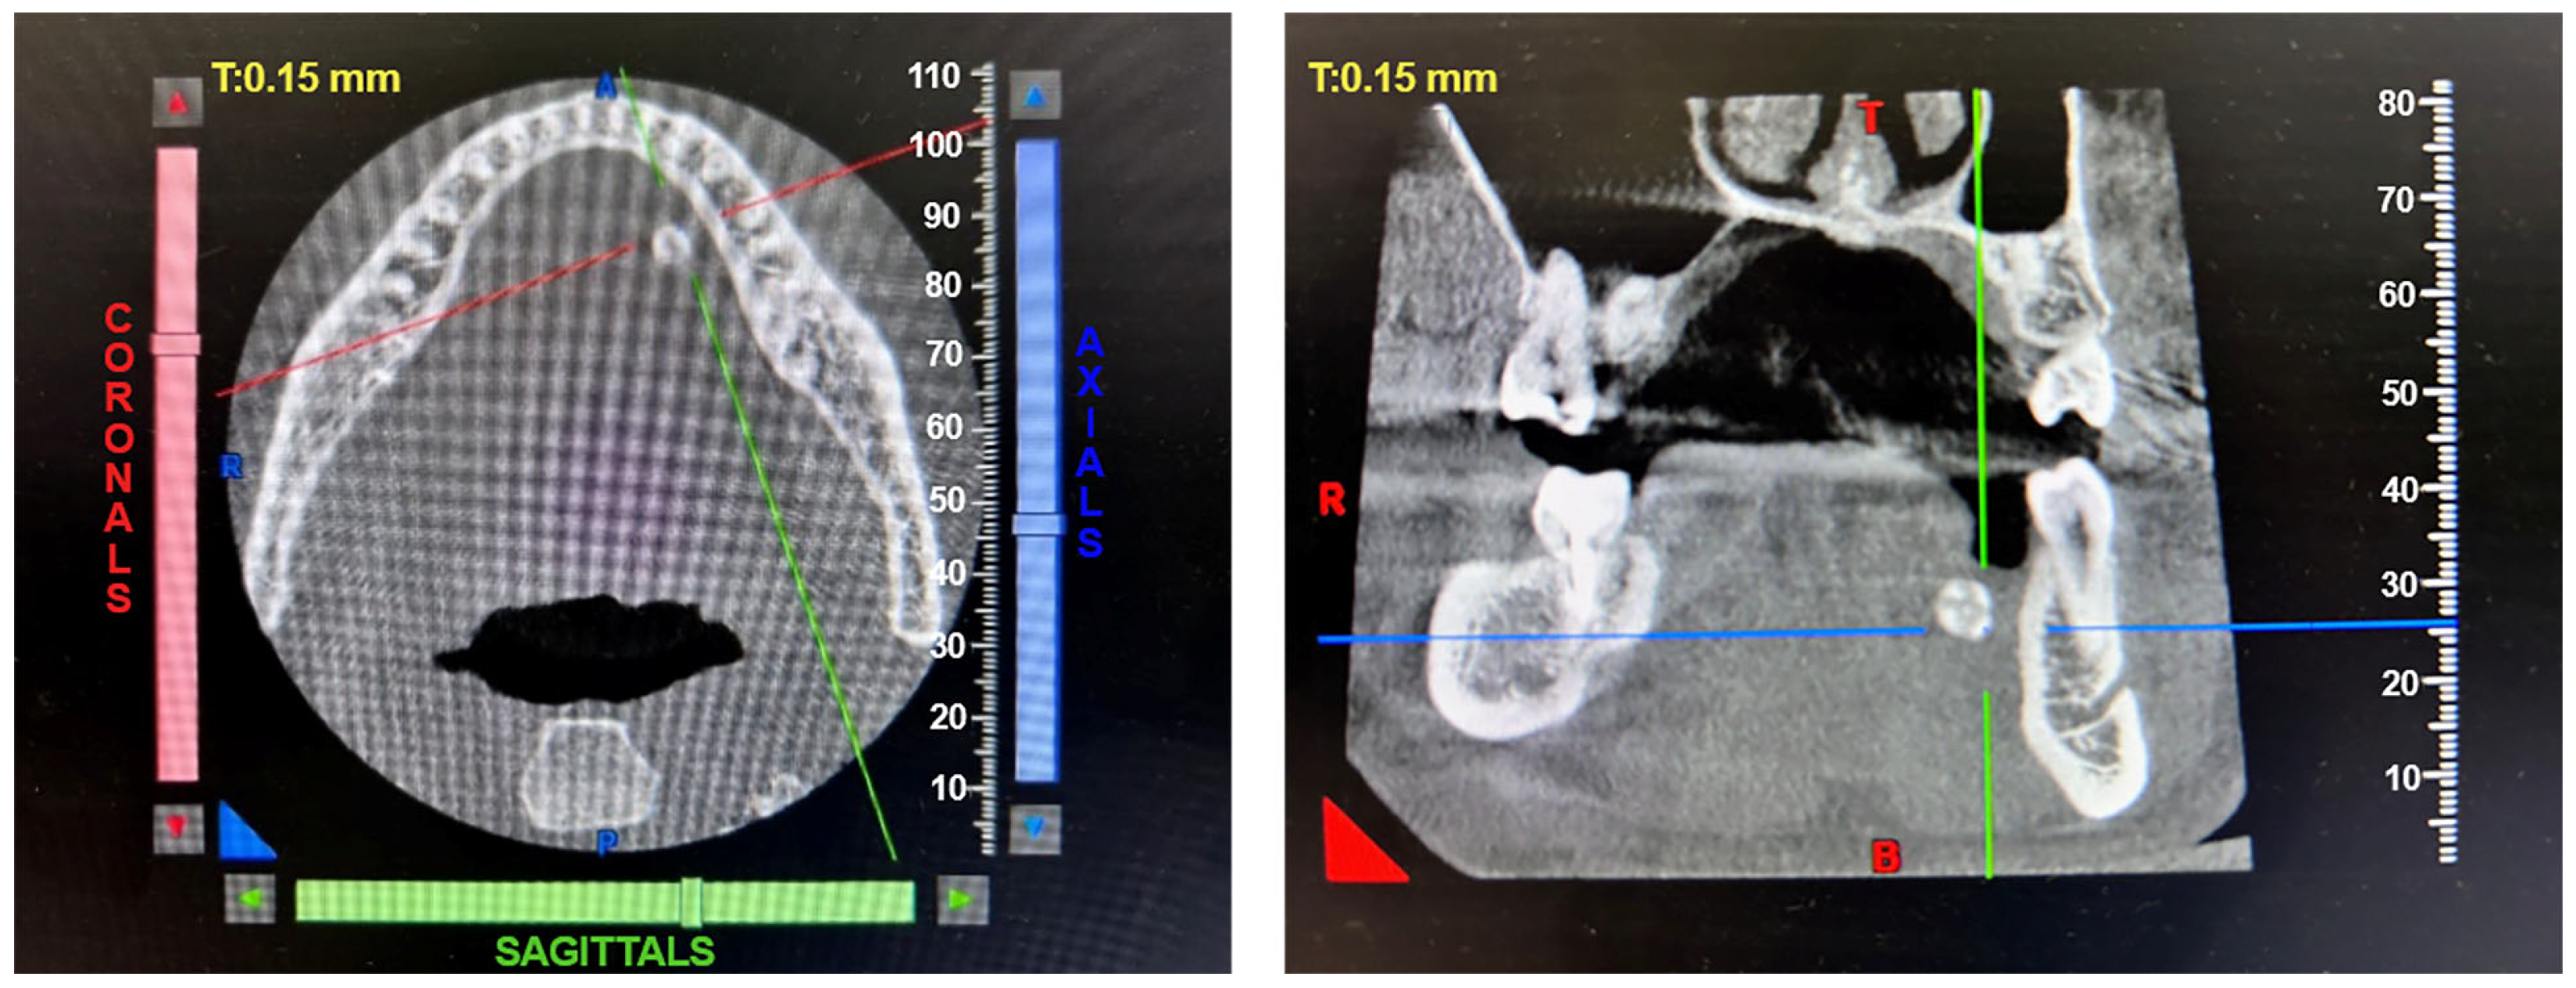

2.1. The Results of X-ray Studies of Salivary Gland Stones

4.2. X-ray Micro-CT

4.3. X-ray Fluorescence Analysis (XRF)